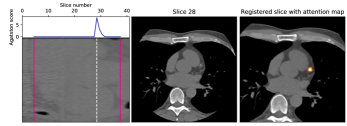

V-C Decision feedback

Decision feedback visualizes attention of the calcium scoring ConvNet. This feedback informs and end-user about the regions that contributed to the calcium score. Figure 7 shows examples of such feedback. The feedback helps an expert to quickly navigate and evaluate the image slices containing CAC.

We propose visual feedback as an optional qualitative tool, but we have performed a quantitative analysis to provide insight in its accuracy. To obtain quantitative results we analyzed heatmaps for slices with predicted calcium scores. The heatmaps were warped to the original image spaces by using the inverse transformation matrices. The values of the heatmaps were scaled between 0 and 1 to mimic probability maps for CAC candidate voxels. CAC candidates were defined as high density 26-connected voxels with a volume between 1.5 and 1,500 mm3[19]. For evaluation of these maps we performed precision-recall analysis (Figure 8). We have defined an optimal threshold by selecting the maximum F1 (i.e. Dice) score on the validation set. Table IV shows the obtained scores using the selected threshold on the test sets. The results show that detection performance is very accurate on the validation set as well as the test set.

Additionally, decision feedback aided our analysis by clarifying incorrect calcium scores. Decision feedback revealed that the largest CVD miscategorizations were not caused by incorrect quantification but by incorrect recognition of CAC. Figure 9 shows six examples of the largest miscategorizations made by the calcium scoring ConvNet. The majority of errors were made in identification of calcifications near the coronary artery ostia. Calcifications near the ostia can be partly in the aorta and partly in the coronary artery. These calcifications are difficult to distinguish, especially when no information of neighboring slices is available.